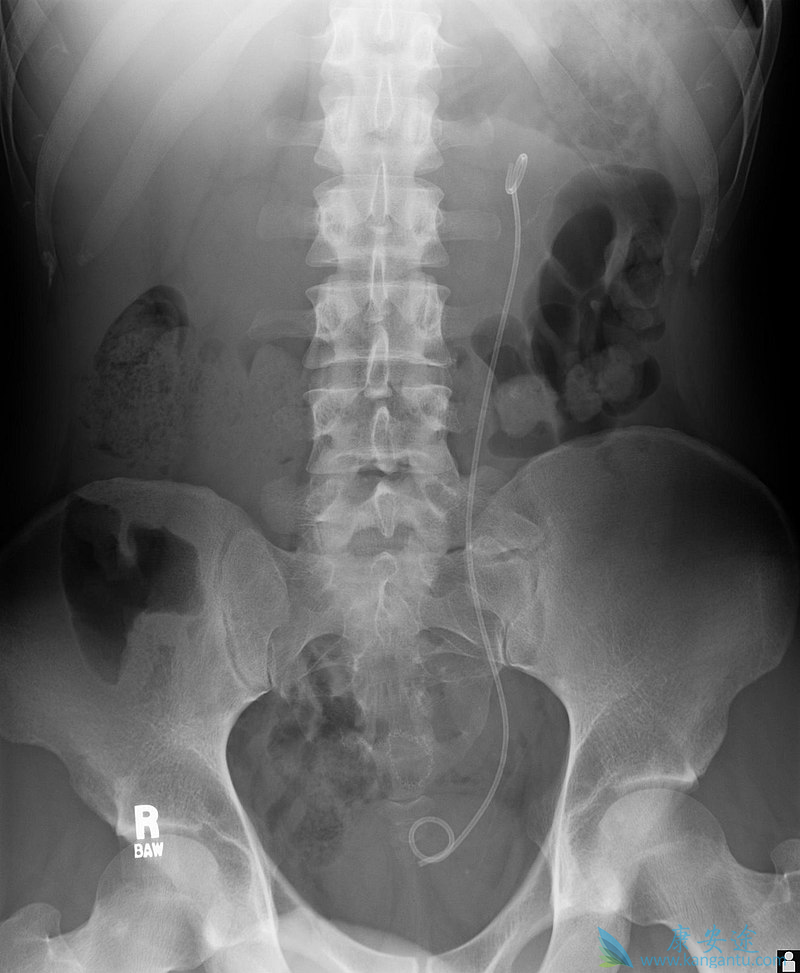

| 输尿管支架用于确保输尿管的通畅,这可能会受到肾结石的损害。这种方法有时被用作临时措施,以防止对被阻止的肾脏造成伤害,直到可以执行去除石块的程序。 |